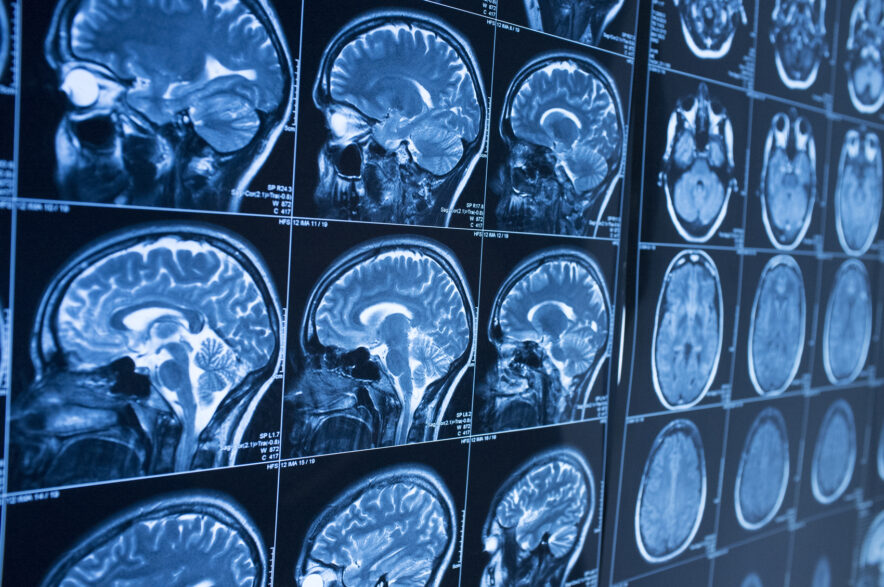

CTE presents as a certain type of dementia, but it can only be diagnosed by performing an autopsy after the afflicted person has died. Contact-sport athletes and parents of young athletes are becoming more educated on CTE and the risks associated with TBIs.

There is currently no method for diagnosing CTE in a living person. After death, doctors can examine the brain and look for a buildup of abnormal tau proteins that indicate the presence of CTE.